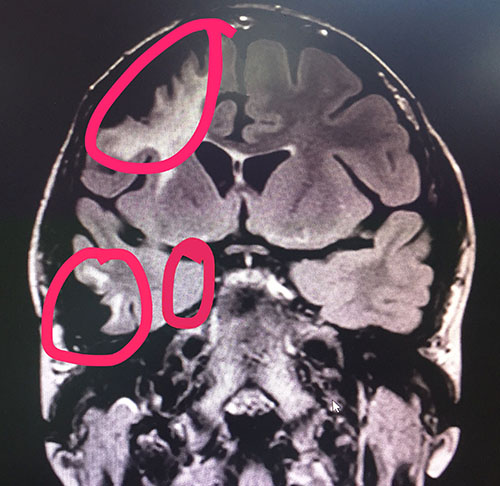

▲标记处为需要进行手术的癫痫病灶区

1、左侧海马信号增高,体积稍变小,考虑海马硬化可能,结合临床。2、MRS 双侧海马Cho峰稍微升高(右侧NAA/Cr+Cho=0.49;左侧NAA/Cr+Cho=0、54)结合临床。3、右侧额叶及颞叶软化灶形成,结合临床病史。

杨忠旭博士亲自为李雪做了手术,但因其有二十多年的癫痫史,又曾在其他医院进行过“颅内电极置入术和右侧额叶致病灶切除术”手术,她大脑部分正常结构已经发生了改变,有三处癫痫病灶区(右侧额极蛛网膜囊肿癫痫病灶区、右侧颞叶癫痫病灶区、右侧海马癫痫病灶区)需要进行手术,如果再次进行手术,就必须小心、小心、再小心,这就为这次手术的进行增加了难度。